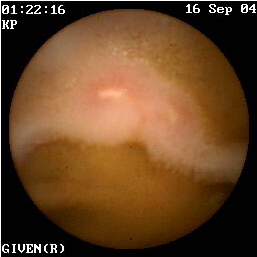

Η κάψουλα έχει επίσης ιδιαίτερη αξία στην ανεύρεση της εστίας της αιμορραγίας αγνώστου αιτιολογίας στη νόσο του Crohn (εικόνες 1,2). Οι Legnaniκαι συν του16 εκτίμησαν 11 ασθενείς με νόσο Crohnκαι αδιευκρίνιστη αιμορραγία και προσδιόρισαν την ακριβή αιτία της στους 9 από αυτούς.

1  2

Eικόνα 1. Βαριά φλεγμονή του βλεννογόνου             Εικόνα 2. Αυτόματη αιμορραγία ειλεού σε ασθενή

με σχηματισμό ψευδοπολύποδα.                             με γνωστή νόσο Crohn